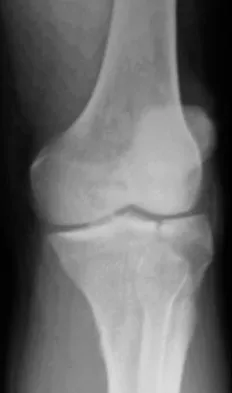

An 8-year-old girl was treated for a Salter-Harris type I fracture of the right distal femur 2 years ago. Examination reveals symmetric knee flexion, extension, and frontal alignment compared to the contralateral knee. She has 1-cm of shortening of the right femur. History reveals that she has always been in the 50th percentile for height, and her skeletal age matches her chronologic age. Radiographs are shown in Figure 9. What is the expected consequence at maturity?

The child has a near complete central physeal arrest of the distal femur and worsening limb-length discrepancy will develop. She is growing at the average rate for the population. The distal femoral physis grows at a rate of roughly 9 mm per year. Girls finish their growth at approximately age 14 years. Thus, at maturity the left leg will be 6.4 cm longer than the right. An angular deformity has not developed at this point and her arrest is central; therefore, angular deformity is unlikely to develop in any plane. Little DG, Nigo L, Aiona MD: Deficiencies of current methods for the timing of epiphysiodesis. J Pediatr Orthop 1996;16:173-179.